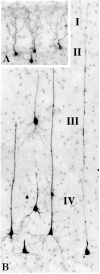

Results: Quantitative evaluation of brain sections revealed a median of 32.5 (range, 18.0-48.2) apoptotic cells/mm of brain tissue in the isoflurane group and only 2.5 (range, 1.1-5.2) in the control group (difference significant at P = 0.008). Apoptotic neuronal profiles were largely confined to the cerebral cortex. In the control brains, they were sparse and randomly distributed, whereas in the isoflurane brains they were abundant and preferentially concentrated in specific cortical layers and regions.